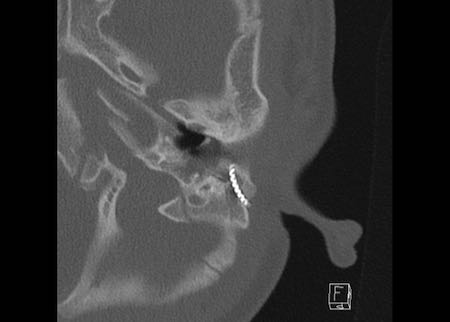

Bên trái là hình ảnh của một bé trai 2 tuổi với teo ống tai ngoài xương hai bên.

Xương búa và xương đe hợp nhất (mũi tên).

Ốc tai bình thường.